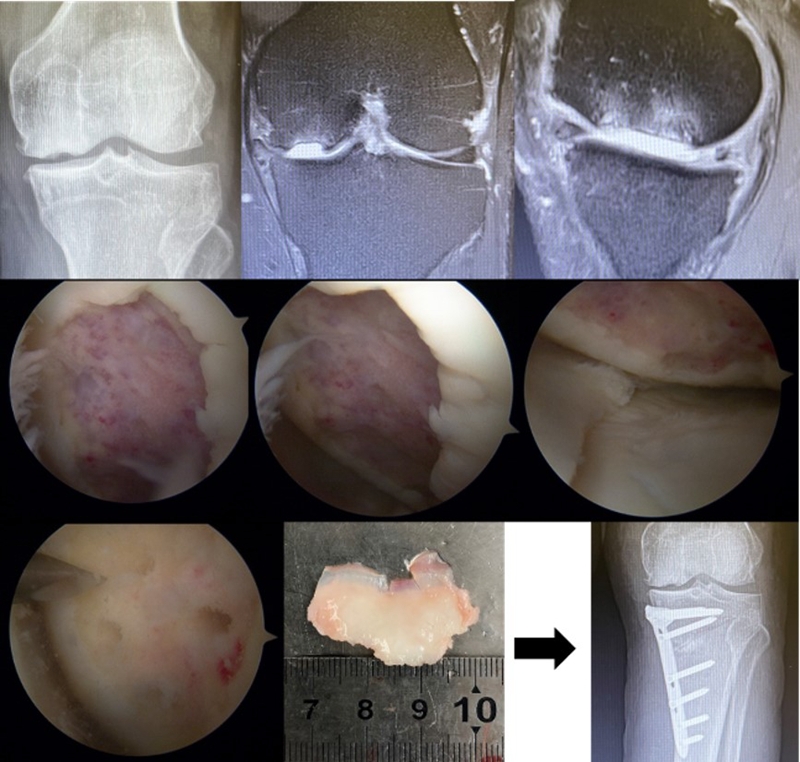

病例3:男,70岁,主诉右膝关节疼痛1年余。查体右膝无肿胀畸形,膝活动度0-120°,内侧间隙压痛。

已经累及44%的股骨内侧髁病变,半月板轻度突出,内侧后角水平撕裂

MRI上深度>20mm

治疗选择保守还是手术?

保守治疗4个月后复查

保守治疗后效果欠佳,坏死范围扩大、塌陷

翻修手术选择截骨矫形还是单髁置换?

最终选择截骨矫形

术后1年1个月

术后2年1个月拆钉

视频3 关节镜探查+拆钉,外侧间室 Outerbridge Ⅱ度

视频4 内侧间室 Outerbridge Ⅲ-Ⅳ度

内侧半月板突出未见明显进展